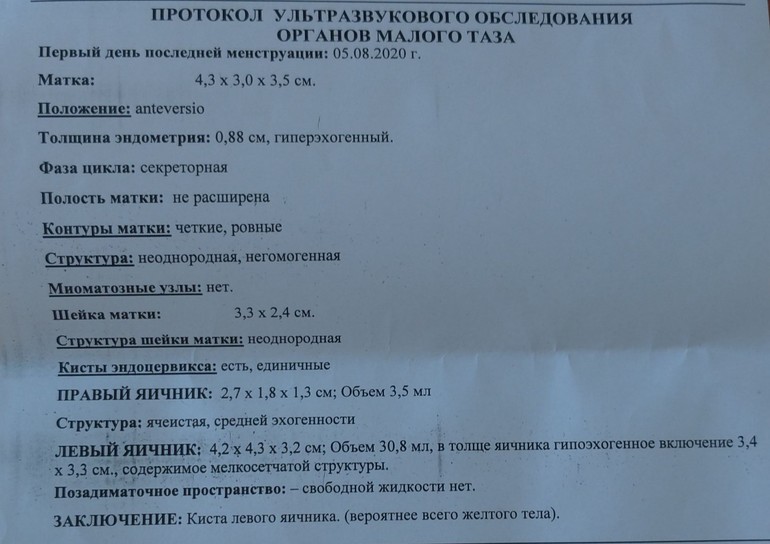

Девочки, всем привет! Была на Узи, так как неделю уже мучают боли снизу слева, думала, что мочевой пузырь, но на УЗИ нашли кисту.

Девочки, всем привет! Была на Узи, так как неделю уже мучают боли снизу слева, думала, что мочевой пузырь, но на УЗИ нашли кисту.

Объясните, пожалуйста, что означает неоднородная, негомогенная структура матки? Это эндометриоз?

извините уж, что прямо фотографию выкладываю, просто у меня бывали кисты фолликулярные, а киста жт впервые. И болит она очень сильно. Прямо режущая боль иногда. Сейчас боюсь, если медикаментозно лечить начну, а окажусь беременной, может ли повлиять на плод, не знаете случайно? Я уж в любом случае схожу к гинекологу)

извините уж, что прямо фотографию выкладываю, просто у меня бывали кисты фолликулярные, а киста жт впервые. И болит она очень сильно. Прямо режущая боль иногда. Сейчас боюсь, если медикаментозно лечить начну, а окажусь беременной, может ли повлиять на плод, не знаете случайно? Я уж в любом случае схожу к гинекологу)